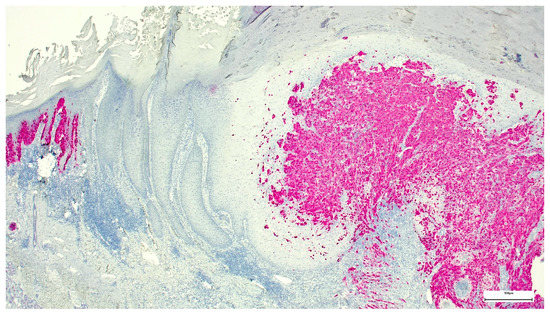

A Wolf in Sheep’s Clothing: Collision of Melanoma and Keratoacanthoma

:1. Case Presentation

2. Discussion